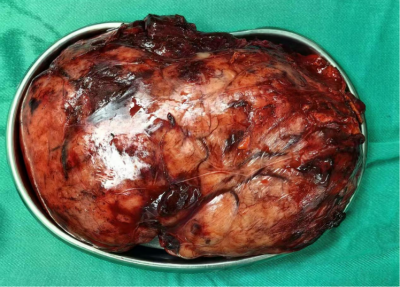

手术由张超副院长主刀,李大爷的“腹腔探查术+腹盆腔巨大肿物切除术”顺利实施。术中发现肿瘤直径15*6.5cm,表面暗红色渗液,自发破裂,腹腔积血约200ml。

根据病理报告显示,患者李大爷腹腔内巨型肿瘤确诊为胃肠道间质瘤。